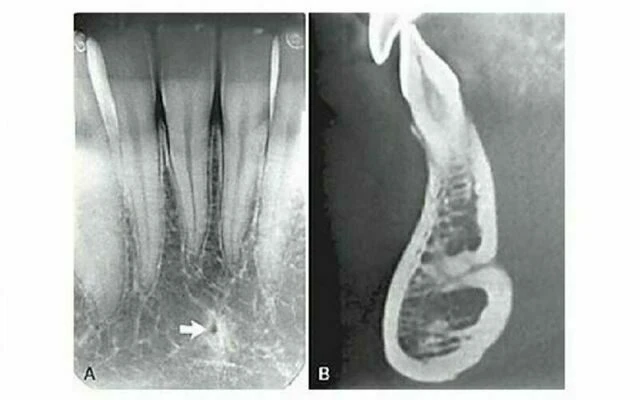

Ống dinh dưỡng

Ống dinh dưỡng chứa một bó thần kinh mạch máu và có hình ảnh dạng đường thấu quang với chiều rộng khá đồng đều. Chúng thường được thấy nhất ở phim quanh chóp ở hàm dưới chạy dọc từ phía dưới ống thần kinh xương ổ răng dưới đến một chóp răng hoặc vào khoảng giữa các răng cửa hàm dưới. Thấy được chúng trong khoảng 5% trường hợp trên tất cả bệnh nhân và thường ở người nam, da đen, người lớn tuổi và những người có huyết áp cao hoặc bệnh lý nha chu tiến triển. Chúng cũng cho thấy gờ xương mỏng, hữu ích khi đánh giá implant. Vì chúng có giải phẫu là khoảng trống bao quanh bởi thành là xương vỏ nên hình ảnh thường cho thấy biên giới xương dày. Đôi khi ống dinh dưỡng vuông góc với xương vỏ cho hình ảnh một vòng tròn thấu quang giống như hình ảnh thấu quang của bệnh lý. Gờ móng Gờ móng là một mào xương không đều nằm nên bề mặt trong của thân xương hàm dưới. Kéo dài từ vùng răng cối lớn thứ ba đến bờ dưới xương hàm dưới vùng cằm, nó đóng vai trò là chỗ bám của cơ hàm móng. Hình ảnh X quang chạy theo chiều nghiêng xuống và ra trước từ vùng răng cối lớn thứ ba đến vùng răng cối nhỏ, ở xấp xỉ mức chóp các răng sau.